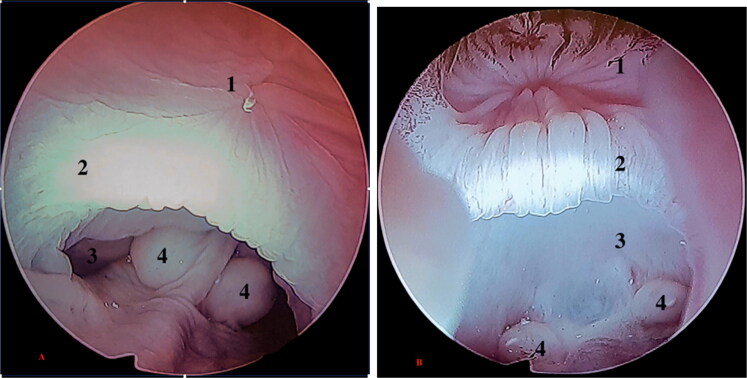

这篇文章首次尝试介绍了在积水马尾鱼(Varananus cumingi)和大马尾鱼(Varananus macraei)泄殖腔区域使用内窥镜技术的实用性和可行性。这种方法既可用于诊断,也可用于治疗,还可通过观察尿道(雄性尿道末端为盲端,雌性尿道末端由两个代表输卵管出口的孔组成),为性别鉴定提供早期方法。在这种情况下,通常采用的性别鉴定技术,如后腔距检测,已显示出不可靠的一面。这项研究对来自一家私人繁殖场的十只约一岁大的标本进行了检查,在此之前还对它们进行了全面的临床评估,以确认它们的总体健康状况。所有受试者都接受了镇静剂治疗,从而可以对解剖结构、泄殖腔健康状况和性别进行评估。这项研究及其发现可为解决这些物种数量下降的问题提供重要依据,尤其是已被世界自然保护联盟列为 "濒危 "物种的大鳞蛙。

This article attempts to present, for the first time, the usefulness and feasibility of using endoscopic techniques in the cloacal region of Varanus cumingi and Varanus macraei. This method can serve both diagnostic and therapeutic purposes, as well as offering an early approach to sex determination through the observation of the urodeum which in males ends in a blind end while in females it consists of two ostia which represent the outlets of the oviducts. In this context, commonly employed sex determination techniques, such as post-cloacal spur detection, have shown unreliability. The study involved the examination of ten specimens, approximately one year old, from a private breeding farm, following a complete clinical evaluation to confirm their general state of health. All subjects underwent sedation, which allowed the evaluation of anatomical structures, the health status of the cloaca and the determination of sex. This study and its findings may provide a critical basis for addressing population declines of these species, particularly for V. macraei, which has already been classified as 'endangered' by the IUCN.